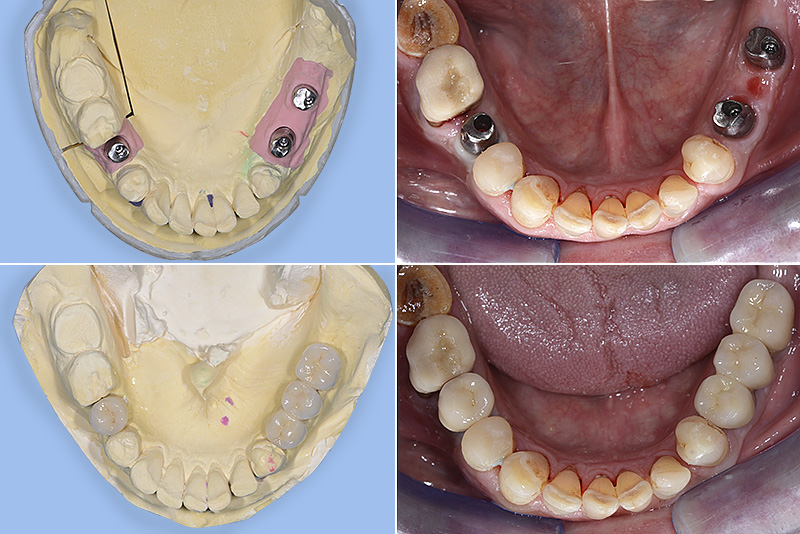

PREMESSA: in seguito all’estrazione dell’incisivo laterale superiore di destra, resasi necessaria per cause batteriche, si decide di affrontare il caso con il posizionamento di un impianto in sostituzione dell’elemento mancante dopo guarigione del sito infetto. Con tecniche rigenerative sia dei tessuti ossei mancanti a causa dell’infezione pregressa, sia dei tessuti gengivali che appaiono inizialmente troppo spostati in alto, si ripristina una corretta morfologia delle parabole (contorni) gengivali e delle papille interdentali (triangoli di gengiva tra due denti vicini).

Vengono utilizzati 2 tipi di provvisori: il primo, cementato ai denti vicini, viene utilizzato dal momento dell’estrazione del dente fino ad impianto osteointegrato (circa 6 mesi); il secondo, avvitato direttamente all’impianto, ha una funzione di prova estetica ma soprattutto di guida per la maturazione dei tessuti gengivali peri-implantari portandoli verso la maturazione completa prima di posizionare la corona finale in disilicato di litio.